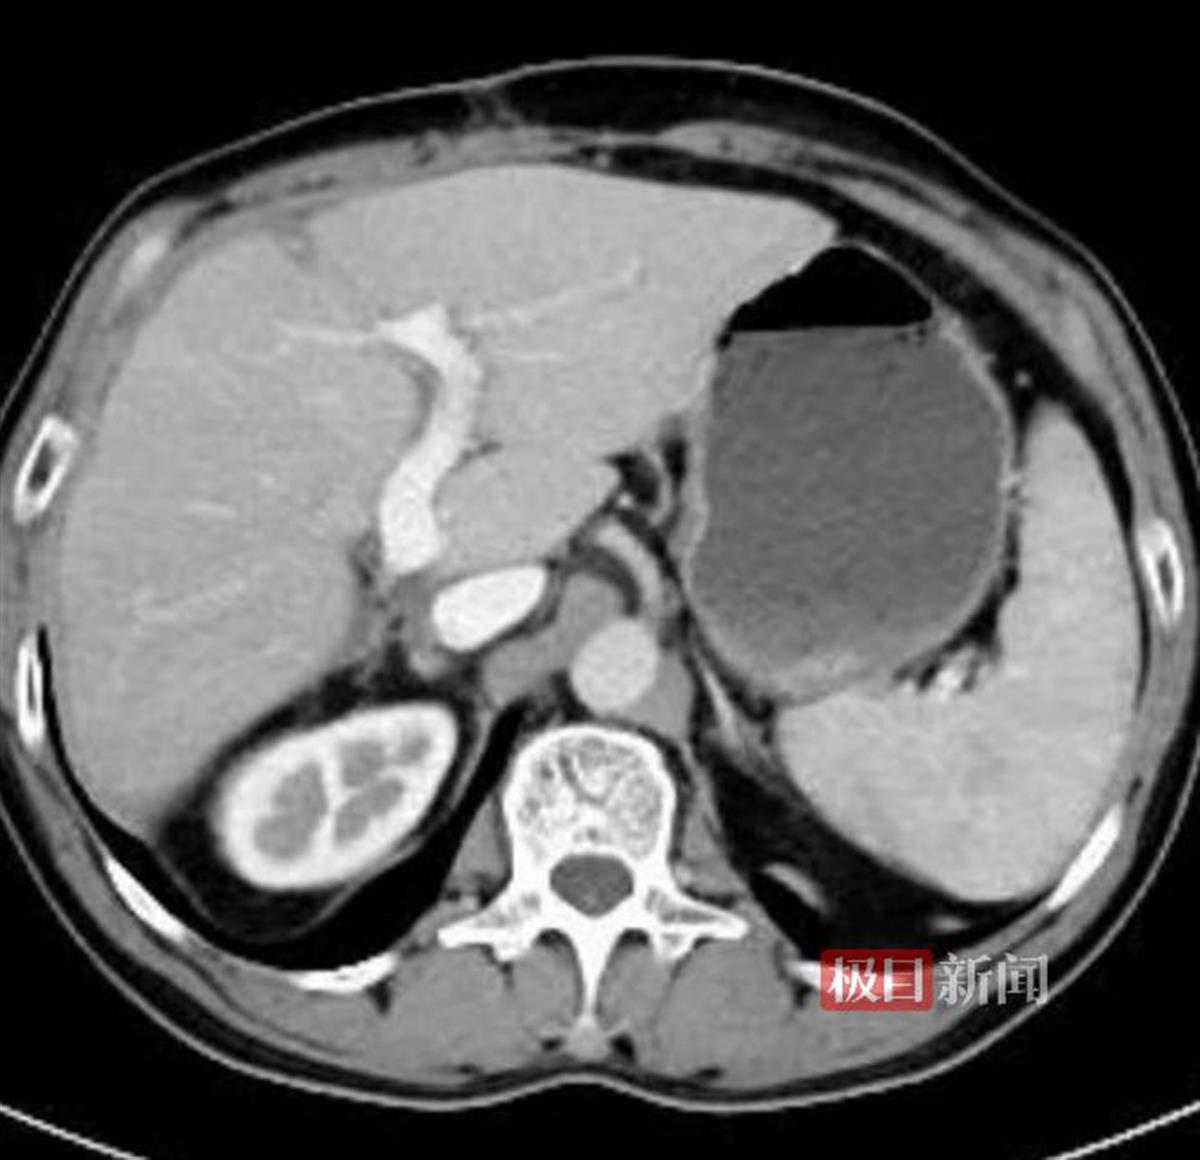

术后3个月复查,肝脏未见异常

胡少勃介绍,即使是60岁的年纪,患者肝脏的再生能力仍很强,在去除肿瘤后,肝脏重约1907克,也比正常的肝脏体积大,完全可以满足机体的需要。